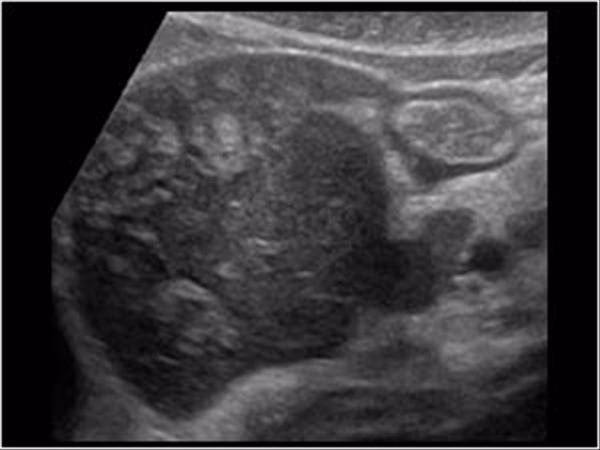

Ved akut kolecystitis (galdeblærebetændelse) vil lægen typisk se en fortykket galdeblærevæg, væske omkring galdeblæren, og ofte en eller flere galdesten, der blokerer galdegangen. Men ved akut viral hepatitis kan ultralydsbilledet på bemærkelsesværdig vis efterligne disse fund. Den primære forskel er ofte fraværet af galdesten. Leverbetændelsen forårsager en reaktiv hævelse (ødem) i den nærliggende galdeblærevæg, hvilket får den til at se fortykket ud på scanningen. Denne galdeblærevægsfortykkelse er et centralt, men ofte misforstået, fund.

Det Vildledende "Dobbeltvægstegn"

Et særligt interessant fund ved hepatitis er det såkaldte "dobbeltvægstegn" (double-wall sign). Dette fænomen opstår, når væske siver ind i lagene af galdeblærevæggen og skaber et mørkere (mindre ekkogent) bånd mellem de lysere (mere ekkogene) indre og ydre lag af væggen. På ultralydsskærmen ser det ud, som om galdeblæren har en dobbelt kontur.

Forestil dig en 38-årig mand med en historik med kronisk Hepatitis C, som kommer på skadestuen med forværrede mavesmerter, kvalme og mørk urin. Hans hud og øjne er tydeligt gule. En POCUS-scanning udføres for at udelukke galdeblæreproblemer. Scanningen viser en markant fortykket galdeblærevæg og det klassiske dobbeltvægstegn, men ingen galdesten. Samtidig viser hans blodprøver skyhøje levertal. En efterfølgende blodprøve for hepatitis bekræfter en ny, akut infektion med Hepatitis A oven i hans kroniske sygdom. Her var ultralydsfundet afgørende for at mistænke en leverrelateret årsag frem for et primært galdeblæreproblem.